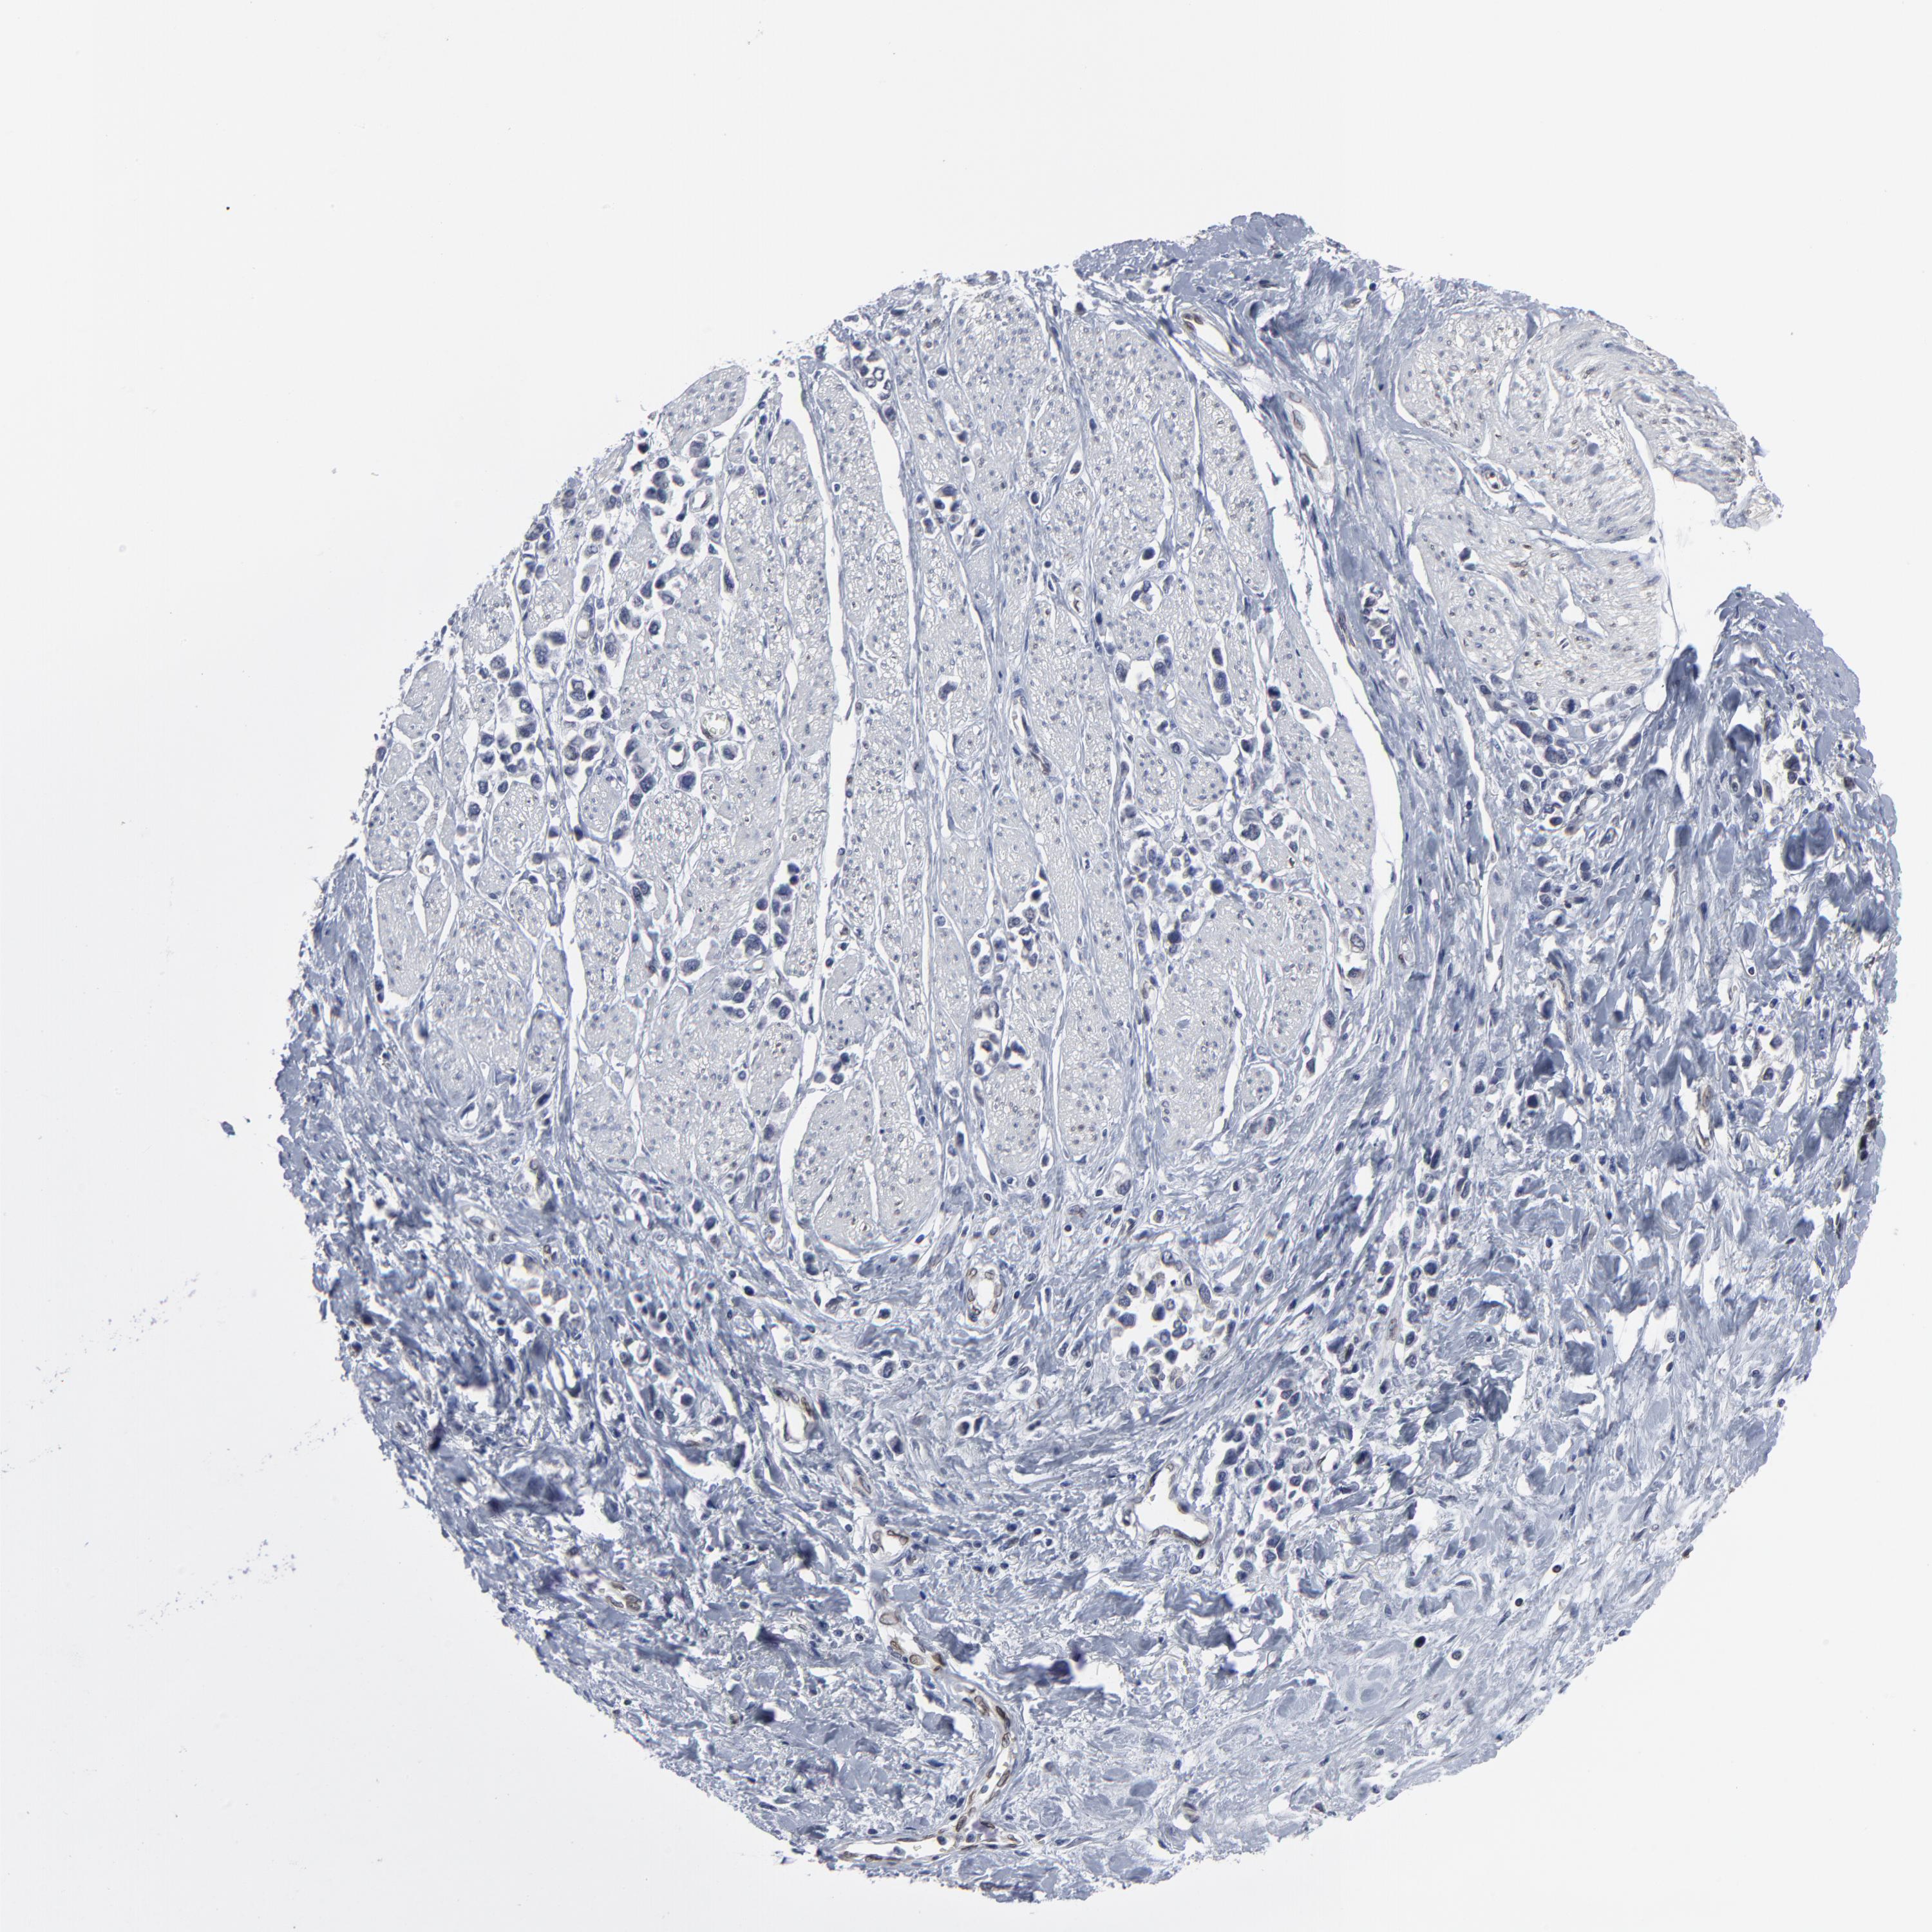

STOMACH CANCER - Protein expressioni

A mouse-over function shows sample information and annotation data. Click on an image to view it in a full screen mode. Samples can be filtered based on level of antibody staining by selecting one or several of the following categories: high, medium, low and not detected. The assay and annotation is described here.

Note that samples used for immunohistochemistry by the Human Protein Atlas do not correspond to samples in the TCGA dataset.

Antibody stainingi

Antibody staining in the annotated cell types in the current human tissue is reported as not detected, low, medium, or high, based on conventional immunohistochemistry profiling in selected tissues. This score is based on the combination of the staining intensity and fraction of stained cells.

Each image is clickable and will lead to virtual microscopy that enables deeper exploration of all samples and also displays staining intensity scores, fraction scores and subcellular localization as well as patient and tissue information for each sample.

Antibody HPA003435

Antibody HPA050204

Staining

High

Medium

Low

Not detected

Intensity

Strong

Moderate

Weak

Negative

Quantity

>75%

75%-25%

<25%

None

Location

Nuclear

Cytoplasmic/membranous

Cytoplasmic/membranous,nuclear

Adenocarcinoma, NOS